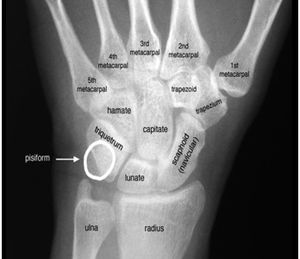

Carpal bones

• Scaphoid fractures account for 70% of all carpal fractures

• Ulnar nerve damage associated with fractures of hamate or pisiform

• 50% of pisiform fracture associated with injury to distal radius or other carpal bone

• If bone fragment seen posterior to carpus on lateral, very likely triquetrum fracture